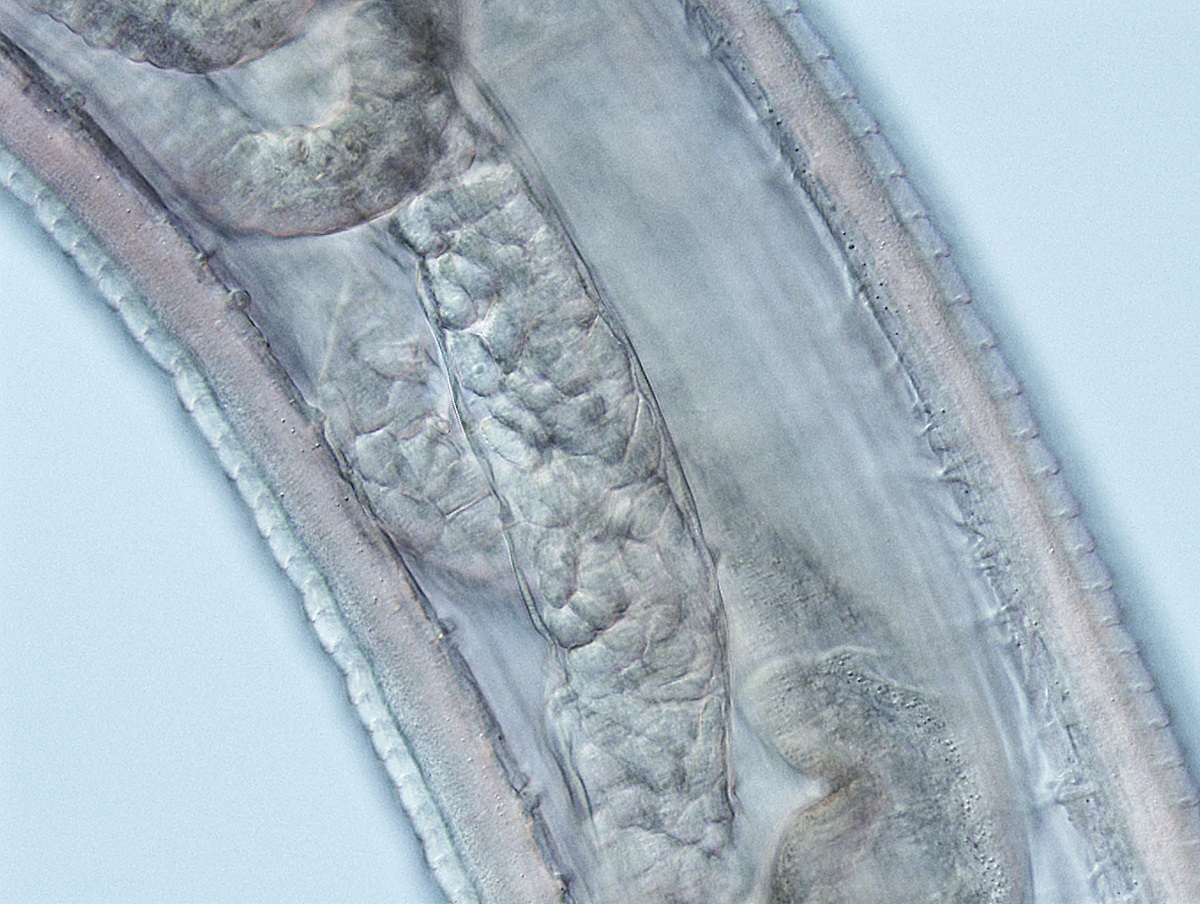

Thelazia gulosa - cattle eyeworm

One of 14 eyeworms removed from Abby Beckley's eye. (Photos courtesy Abby Beckley)

Worms in the family Thelazia are a common parasite in North American cattle, but are rarely spread to humans. Before this case, there were just 10 known incidences of humans being infected with a Thelazia worm in North America, but none of those cases involved the species gulosa. This was the first case of a person being infected with a Thelazia worm in the U.S. in more than two decades.

Luckily, the cattle eyeworm can’t easily reproduce in humans -- and didn’t in Beckley’s case. However, the deposited larvae did grow into adult worms and begin wriggling around on the surface of the Beckley’s eye. She had recently started working on a fishing boat in Alaska when her eye first began to feel irritated, as if there was an eyelash she couldn’t remove.

While examining her eye, Beckley was able to remove a thin, half-inch-long translucent worm with her fingers. She initially thought it might have been a salmon worm, but she couldn’t find any online reports of people who fish with worms in their eyes. She saw a few doctors while she was onshore in Alaska, but no one knew what to do.

Frustrated, Beckley cut her fishing stint short and flew home to Oregon. Bonura met her at the OHSU Emergency Department and worked with other OHSU staff to help Beckley find some relief. Unfortunately, Beckley was the most skilled at plucking out her own worms. Only one doctor was able to pick out a portion of just one worm. All in all, 14 worms were removed from Beckley’s eye over the course of a month.